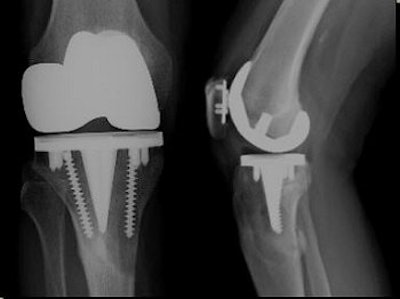

![]() |

| Femoral components that may give rise to artifacts include cobalt chrome with polyethylene tip composition (most common), alumina ceramic, and Oxinium. |

The presence of metallic or ceramic components has limited the value of MR in assessing particle disease, but there ways around this issue, he said. First, he suggested that widening the receiver bandwith may decrease the size of artifacts, citing one study in which artifacts were reduced by 60% because a widened bandwith allowed for a broader range of frequencies to be sampled (Journal of Magnetic Resonance Imaging, September 2004, Vol. 21:7, pp. 745-753).

Other technical tips that can make MRI of prostheses components feasible include increasing the number of excitations to compensate for the loss of signal-to-noise ratio, and increasing the number of refocusing pulses, which decreases the time for intravoxel dephasing. Also, widening the slice-select bandwidth may decrease misregistration between slices. Finally, view angle tilting (VAT) can be used to reduce metal artifacts, Beall said.